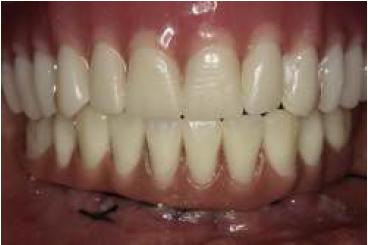

Al tercer día se realizó la instalación con torque manual y ajuste oclusal (figs. 13,14,15,16).

A los 10 días, luego de la cirugía, se citó a la paciente a control para realizar la retirada de la sutura11; se dio torque a los tornillos protésicos (10 N/cm) y se chequeó la oclusión nuevamente. Se ha seguido controlando a la paciente cada 6 meses, hasta cumplir 2 años desde la fecha de instalación de la aparatología, sin manifestar complicación alguna (figs. 17, 18, 19, 20, 21).

Se puede observar un control adecuado de biofilm por parte de la paciente.